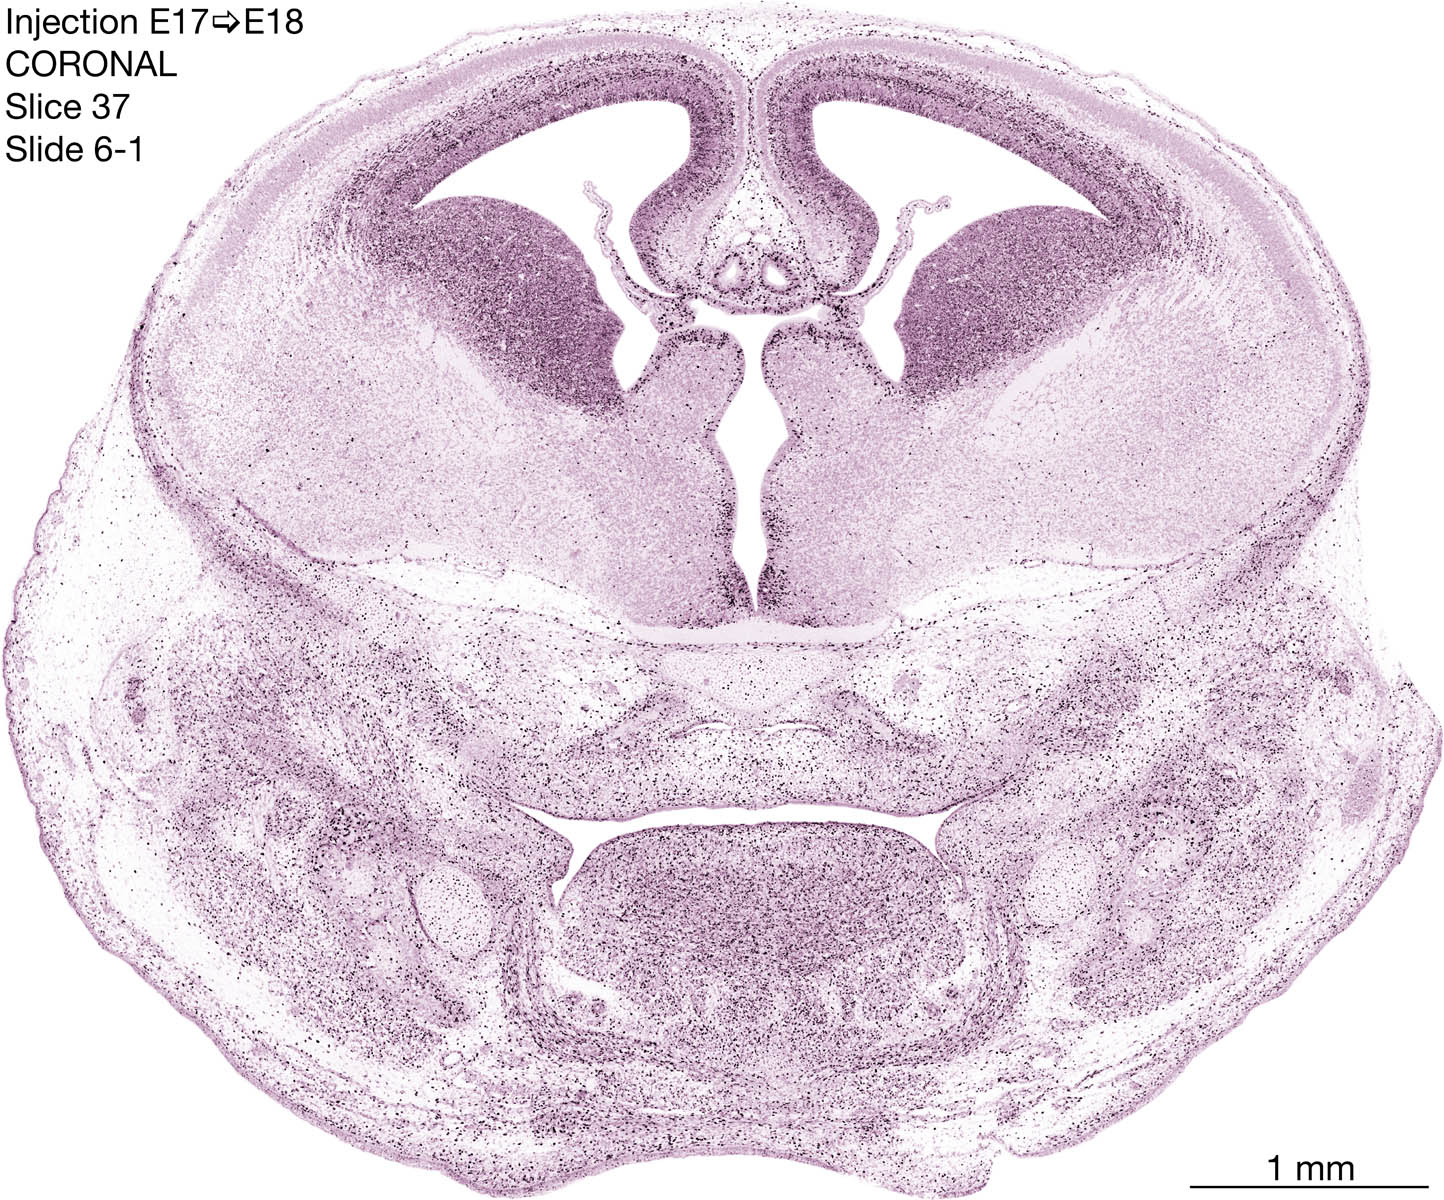

E17 to E18 Survival Archived Images-Coronal

The following images are from a coronally-sectioned head of an E18 rat embryo exposed to tritiated thymidine on E17–24 hr survival.  Note the heavily-labeled cells just outside the germinal zones are now mainly in the diencephalon and forebrain.  These are postmitotic young neurons generated ON E17.  Note that the banded labeling is prominent outside the neocortical neuroepithelium.  Many of the germinal zones in the brainstem have become transformed into the primitive ependyma, and the entire brainstem is becoming more mature; the only primitive area is the cerebellum, where the external germinal layer is now more prominent.